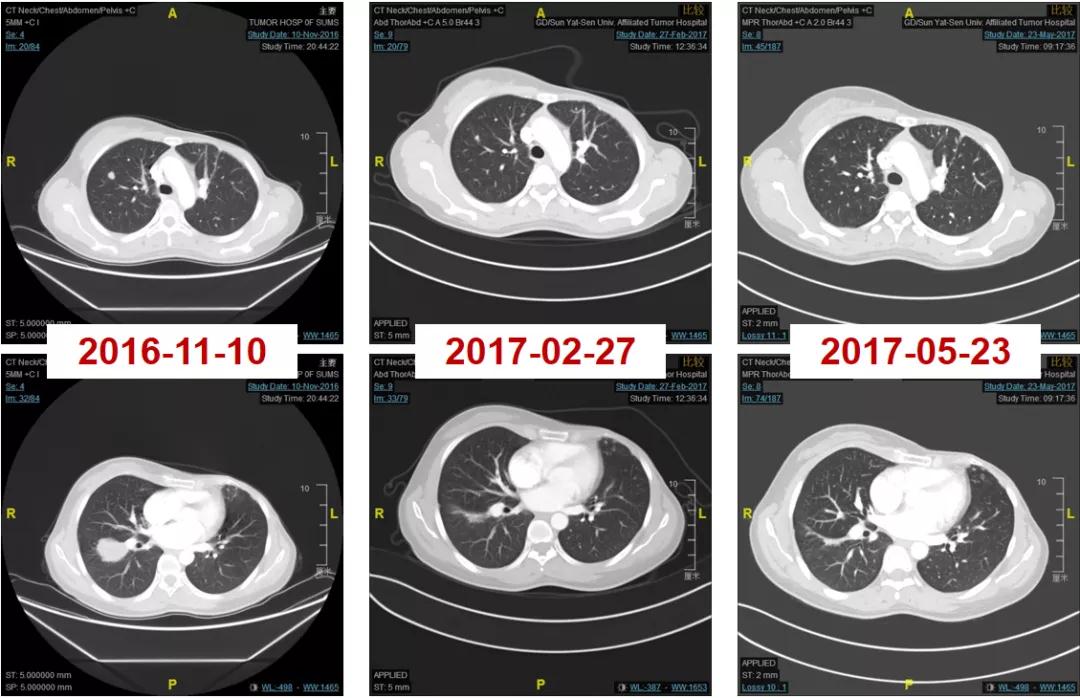

2016-12-06开始使用T-DM1(恩美曲妥珠单抗)方案治疗,首次疗效评估PR,后续最佳疗效CR(图2-3)。

图2

图3